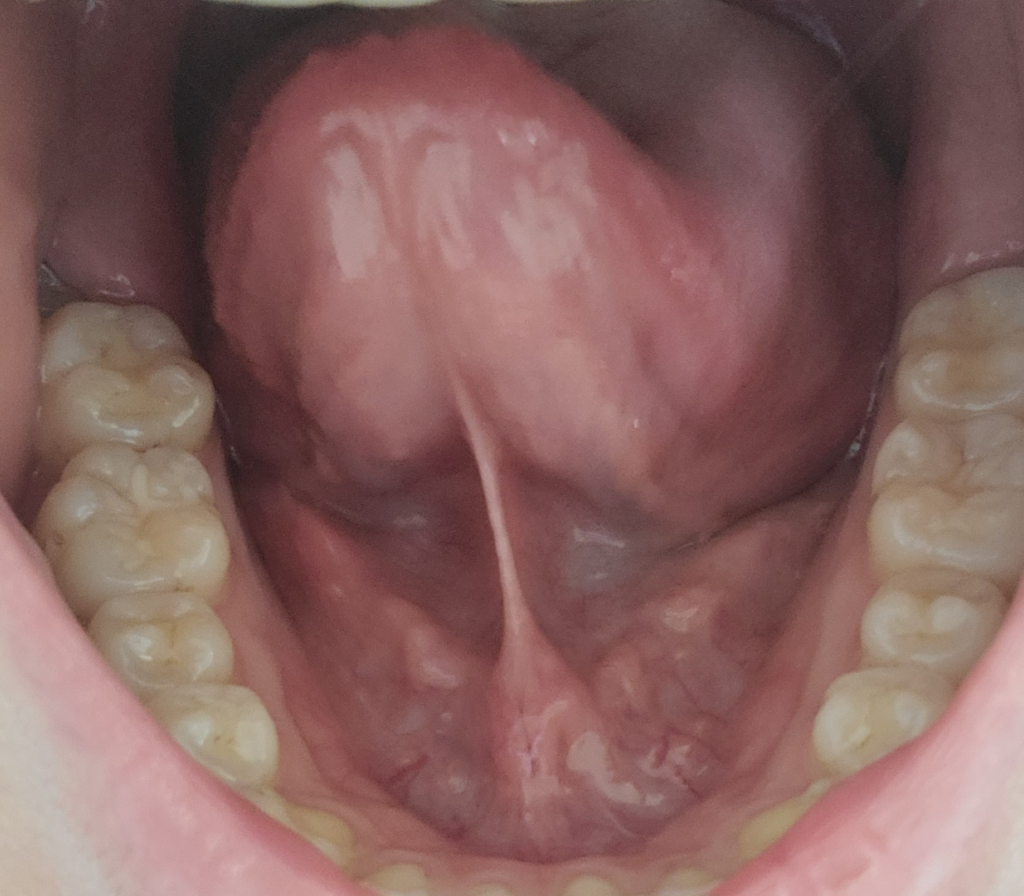

혀 밑 쪽에 돌기가 생겼는데 괜찮은 걸까요?

옆쪽에 저렇게 돌기들이 생겼고 혀 옆에 구내염 이 생겼어요 입안에 염증들이 생긴거 같은데 이거 괜찮은거 맞을까요?ㅠㅠ

구내염 말고는 통증이 없어요

입 안에 구내염 등의 원인으로 염증이 발생하면 림프절들이 커질 수 있는데, 입 아래에 보이는 덩이들이 그러한 반응을 보인 림프절일 수 있겠습니다. 구내염이 호전되면서 함꼐 호전되면 걱정하실 부분은 없겠고, 만약 덩이로 보이는 부분이 자꾸 커지는 것 같다면 이비인후과를 방문하셔야 합니다.

• 사진의 소견을 통해서 보았을 때에는 돌기에 대해서는 애매하며 구내염의 경우에는 충분한 휴식 및 컨디션 조절을 통해서 회복이 가능할 것으로 사료됩니다. 우려스러우시다면 이비인후과에서 보다 정밀하게 검진을 받아보아 이상이 있는지 감별해보시는 것이 필요해 보입니다.